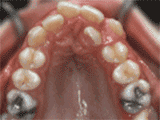

牙列拥挤,牙槽骨过窄,牙齿没有足够空间,只好前后左右高低上下乱长,经过矫正后的牙齿是这样的~